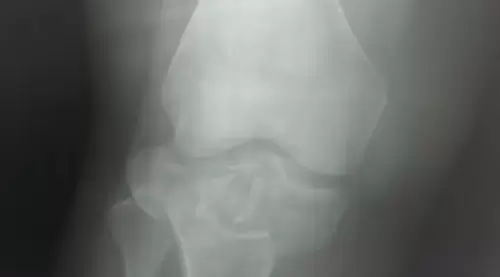

Как сообщает "Вести: Приморье" со ссылкой на Минздрав Приморья, благодаря оперативной и слаженной работе бригады скорой медицинской помощи удалось спасти молодую девушку с крайне тяжёлыми травмами. Пострадавшую экстренно доставили в Спасскую городскую больницу, в травматологическое отделение. Состояние пациентки оценивалось как крайне тяжёлое: травматический шок, открытые переломы костей голени, множественные переломы таза, обширные рваные раны нижних конечностей.

После стабилизации состояния врачи провели сложнейшее оперативное вмешательство — выполнены наружная и внутренняя фиксация переломов таза и голени, лапароскопия для исключения повреждений внутренних органов, а также первичная хирургическая обработка ран. Операция прошла без осложнений», – рассказали специалисты больницы. После этапа реанимации, по согласованию с краевыми медицинскими учреждениями, пациентку перевели в Краевую клиническую больницу №2 для дальнейшей реабилитации.